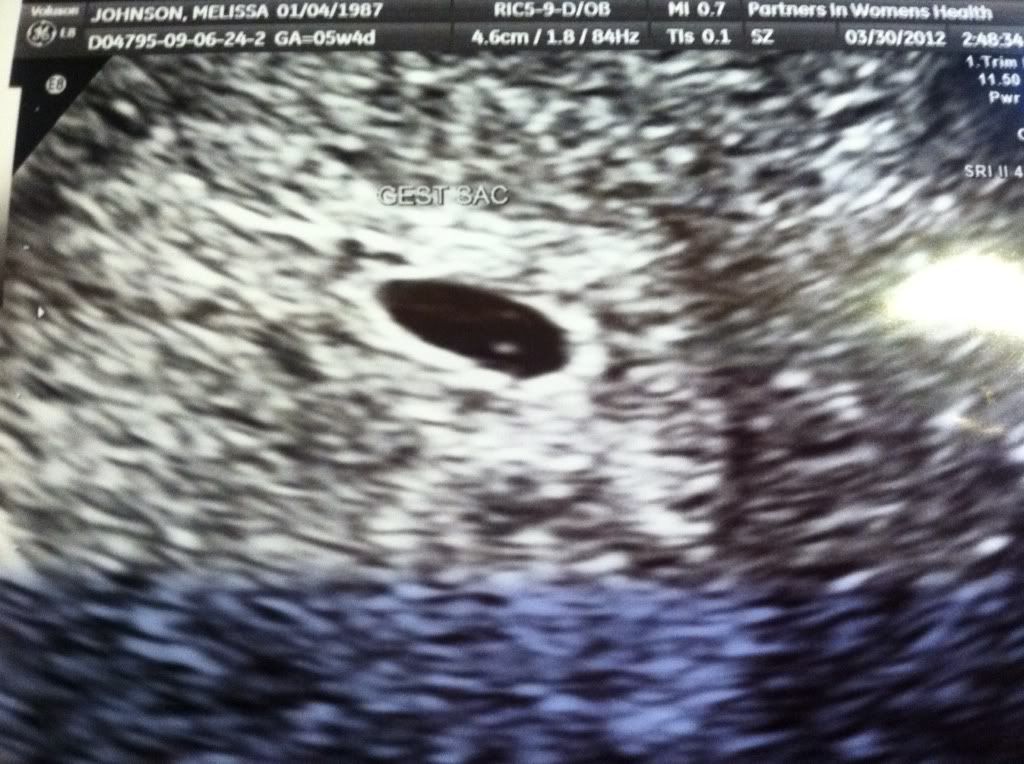

Ultraounds #2,3,4&5...and Announcment